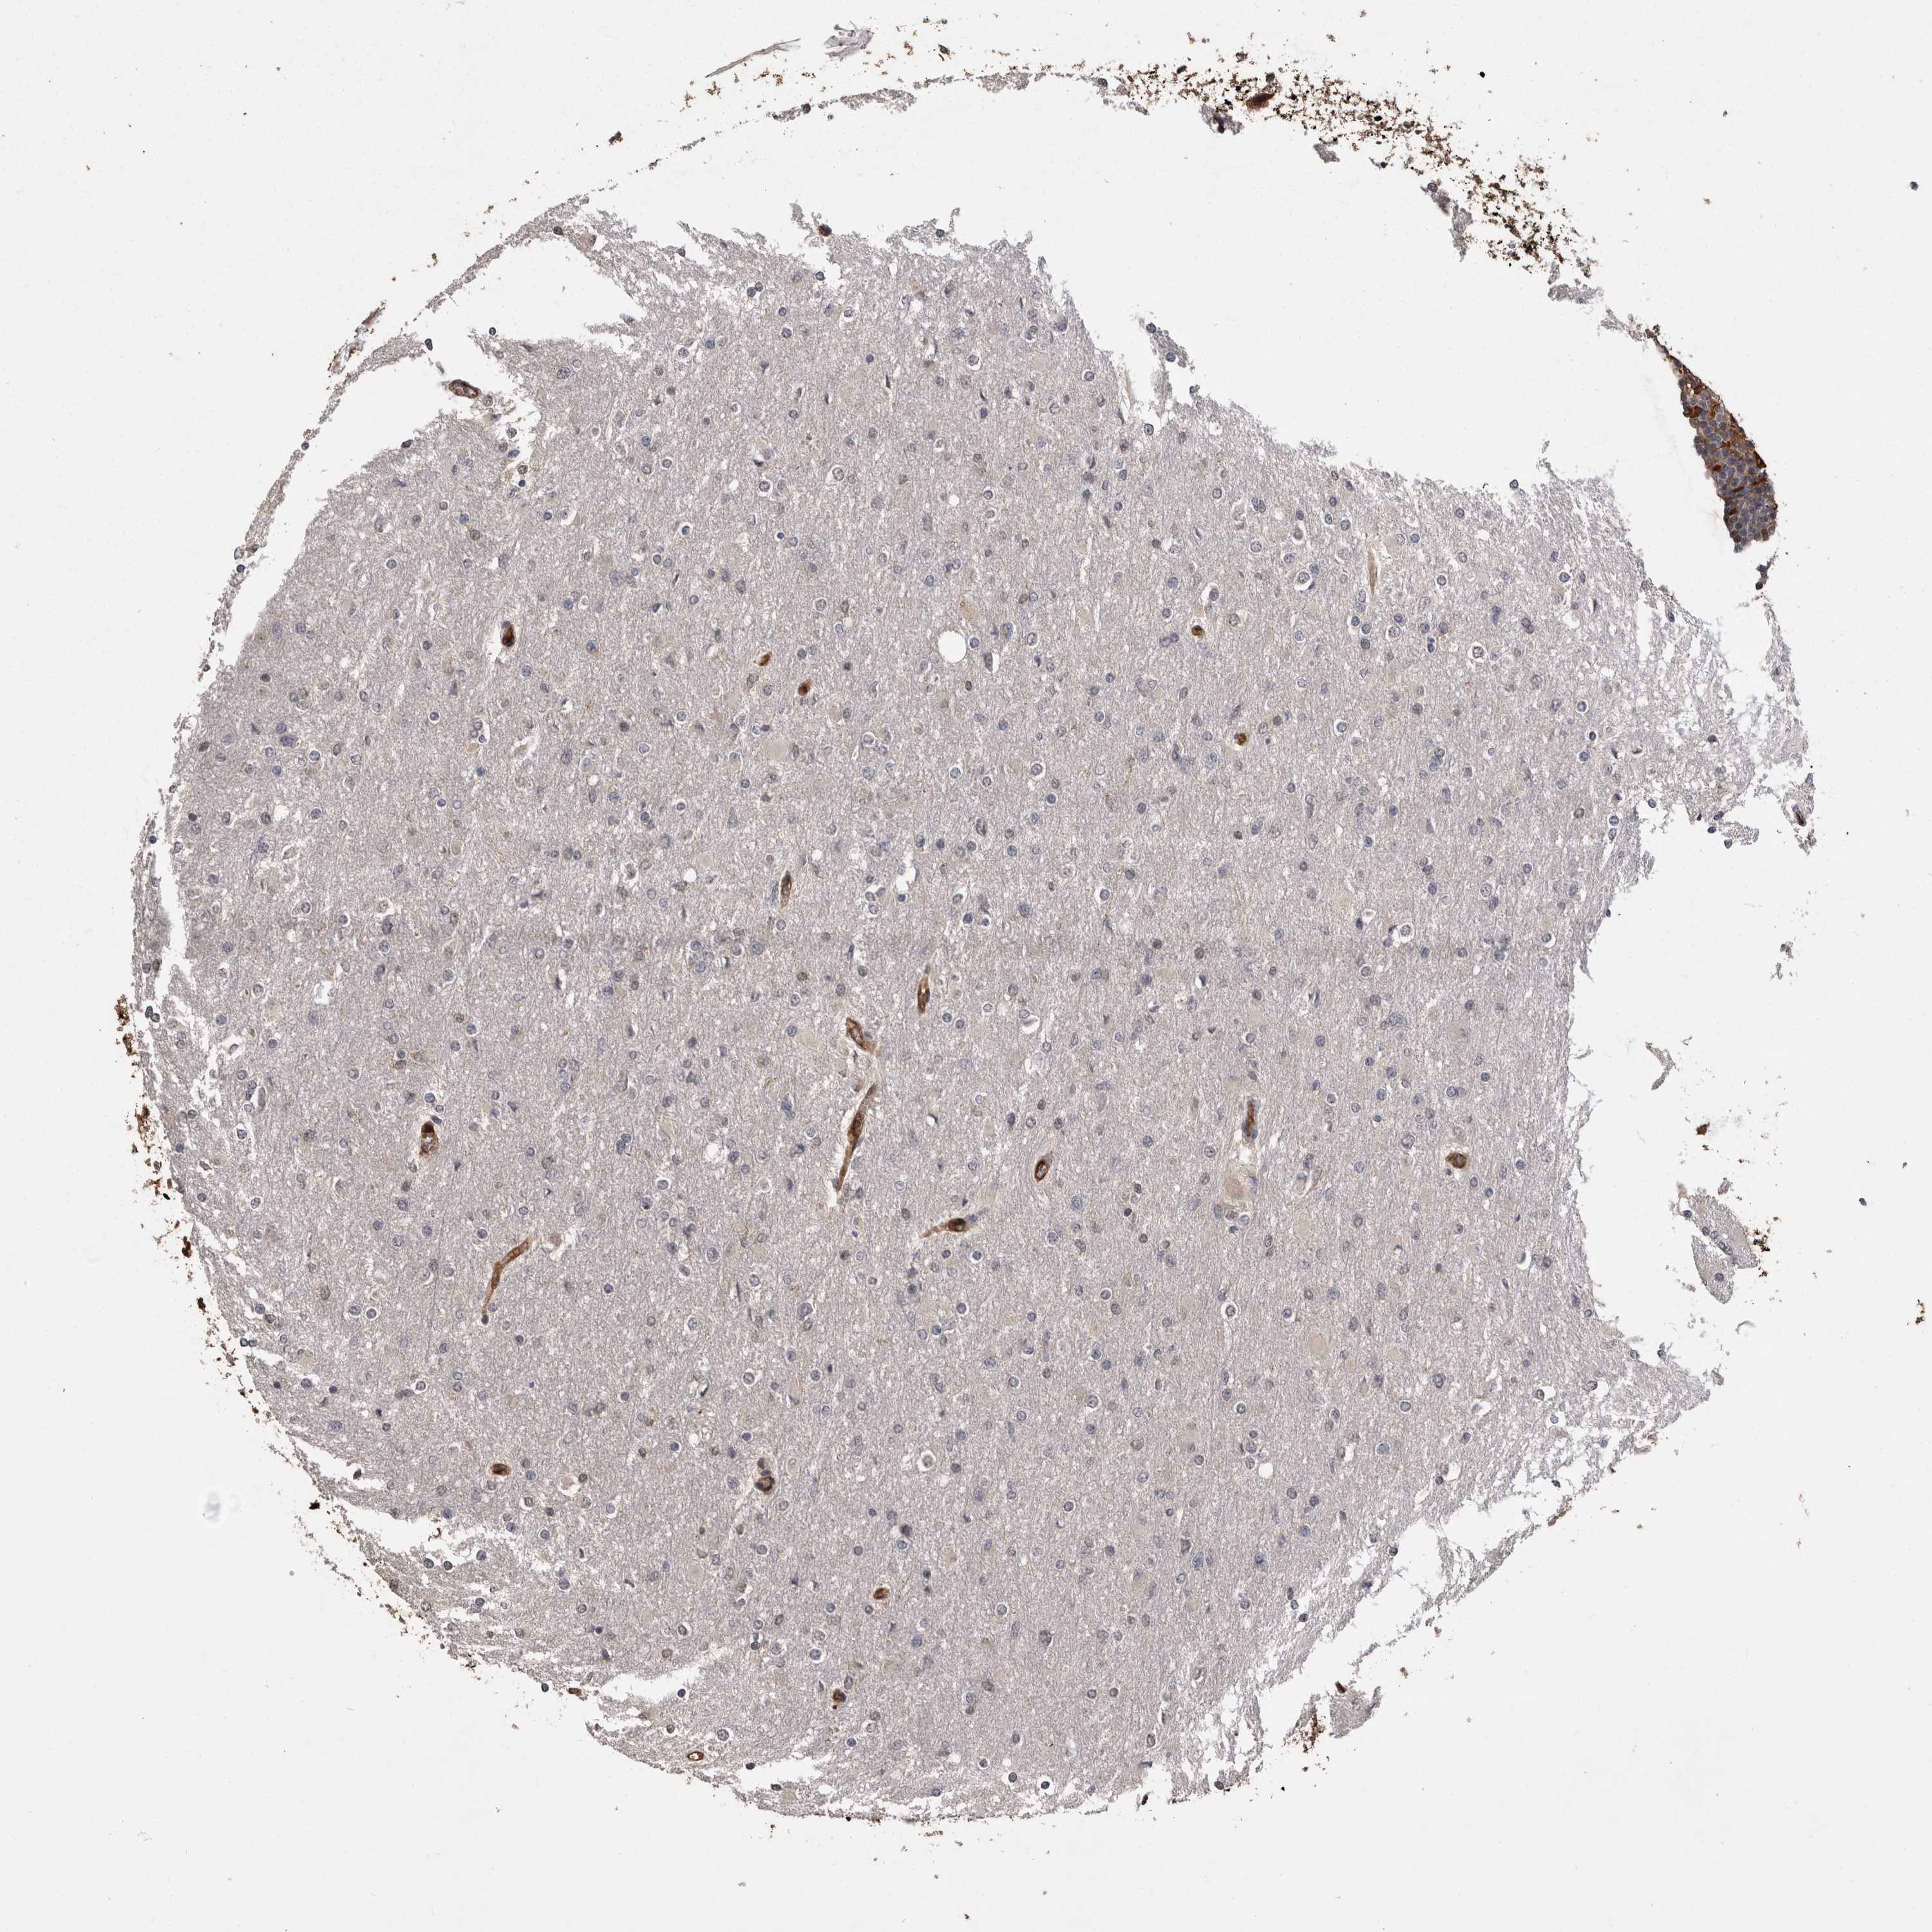

GLIOMA - Protein expressioni

A mouse-over function shows sample information and annotation data. Click on an image to view it in a full screen mode. Samples can be filtered based on level of antibody staining by selecting one or several of the following categories: high, medium, low and not detected. The assay and annotation is described here.

Note that samples used for immunohistochemistry by the Human Protein Atlas do not correspond to samples in the TCGA dataset.

Antibody stainingi

Antibody staining in the annotated cell types in the current human tissue is reported as not detected, low, medium, or high, based on conventional immunohistochemistry profiling in selected tissues. This score is based on the combination of the staining intensity and fraction of stained cells.

Each image is clickable and will lead to virtual microscopy that enables deeper exploration of all samples and also displays staining intensity scores, fraction scores and subcellular localization as well as patient and tissue information for each sample.

Antibody HPA014179

Antibody CAB025128

Staining

High

Medium

Low

Not detected

Intensity

Strong

Moderate

Weak

Negative

Quantity

>75%

75%-25%

<25%

None

Location

Nuclear

Cytoplasmic/membranous

Cytoplasmic/membranous,nuclear

Glioma, malignant, High grade

Glioma, malignant, Low grade